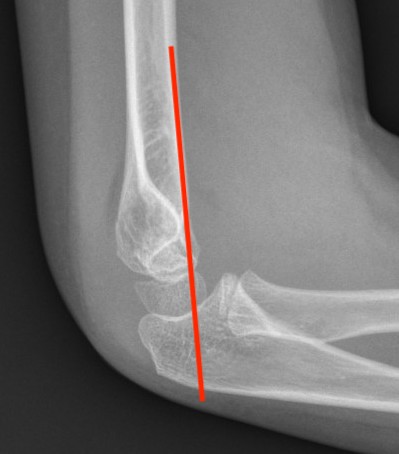

Lateral Xray

Position for good lateral

- thumb vertical

- hand above elbow

Anterior angulation

- shaft - condylar axis

- normally 40o

Lines

Anterior humeral line (AHL)

- should pass through middle of capitellum

Radio-capitellar line

- pass through capitellum

Teardrop

- shadow above the capitellum

- anterior dense line: posterior margin of the coronoid fossa

- posterior dense line: anterior margin of the olecranon fossa

- inferior portion: ossification center of the capitellum